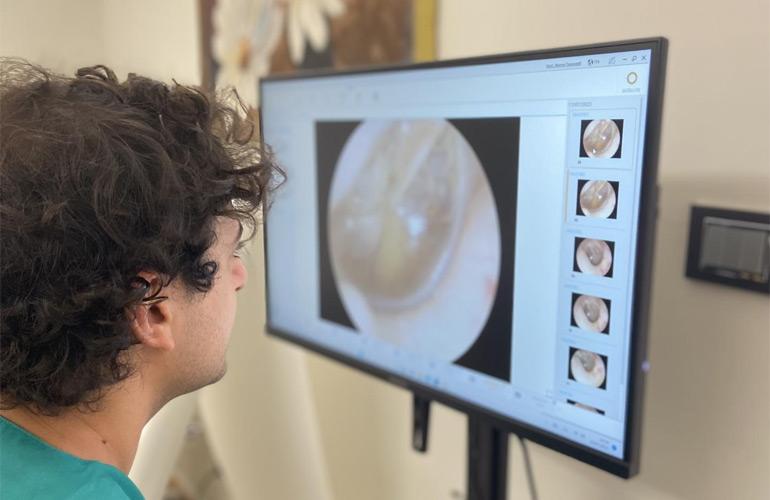

In questo studio medico è possibile eseguire l'otomicroscopia.

L'otomicroscopia è l'indagine del…

L'otomicroscopia è l'indagine del…